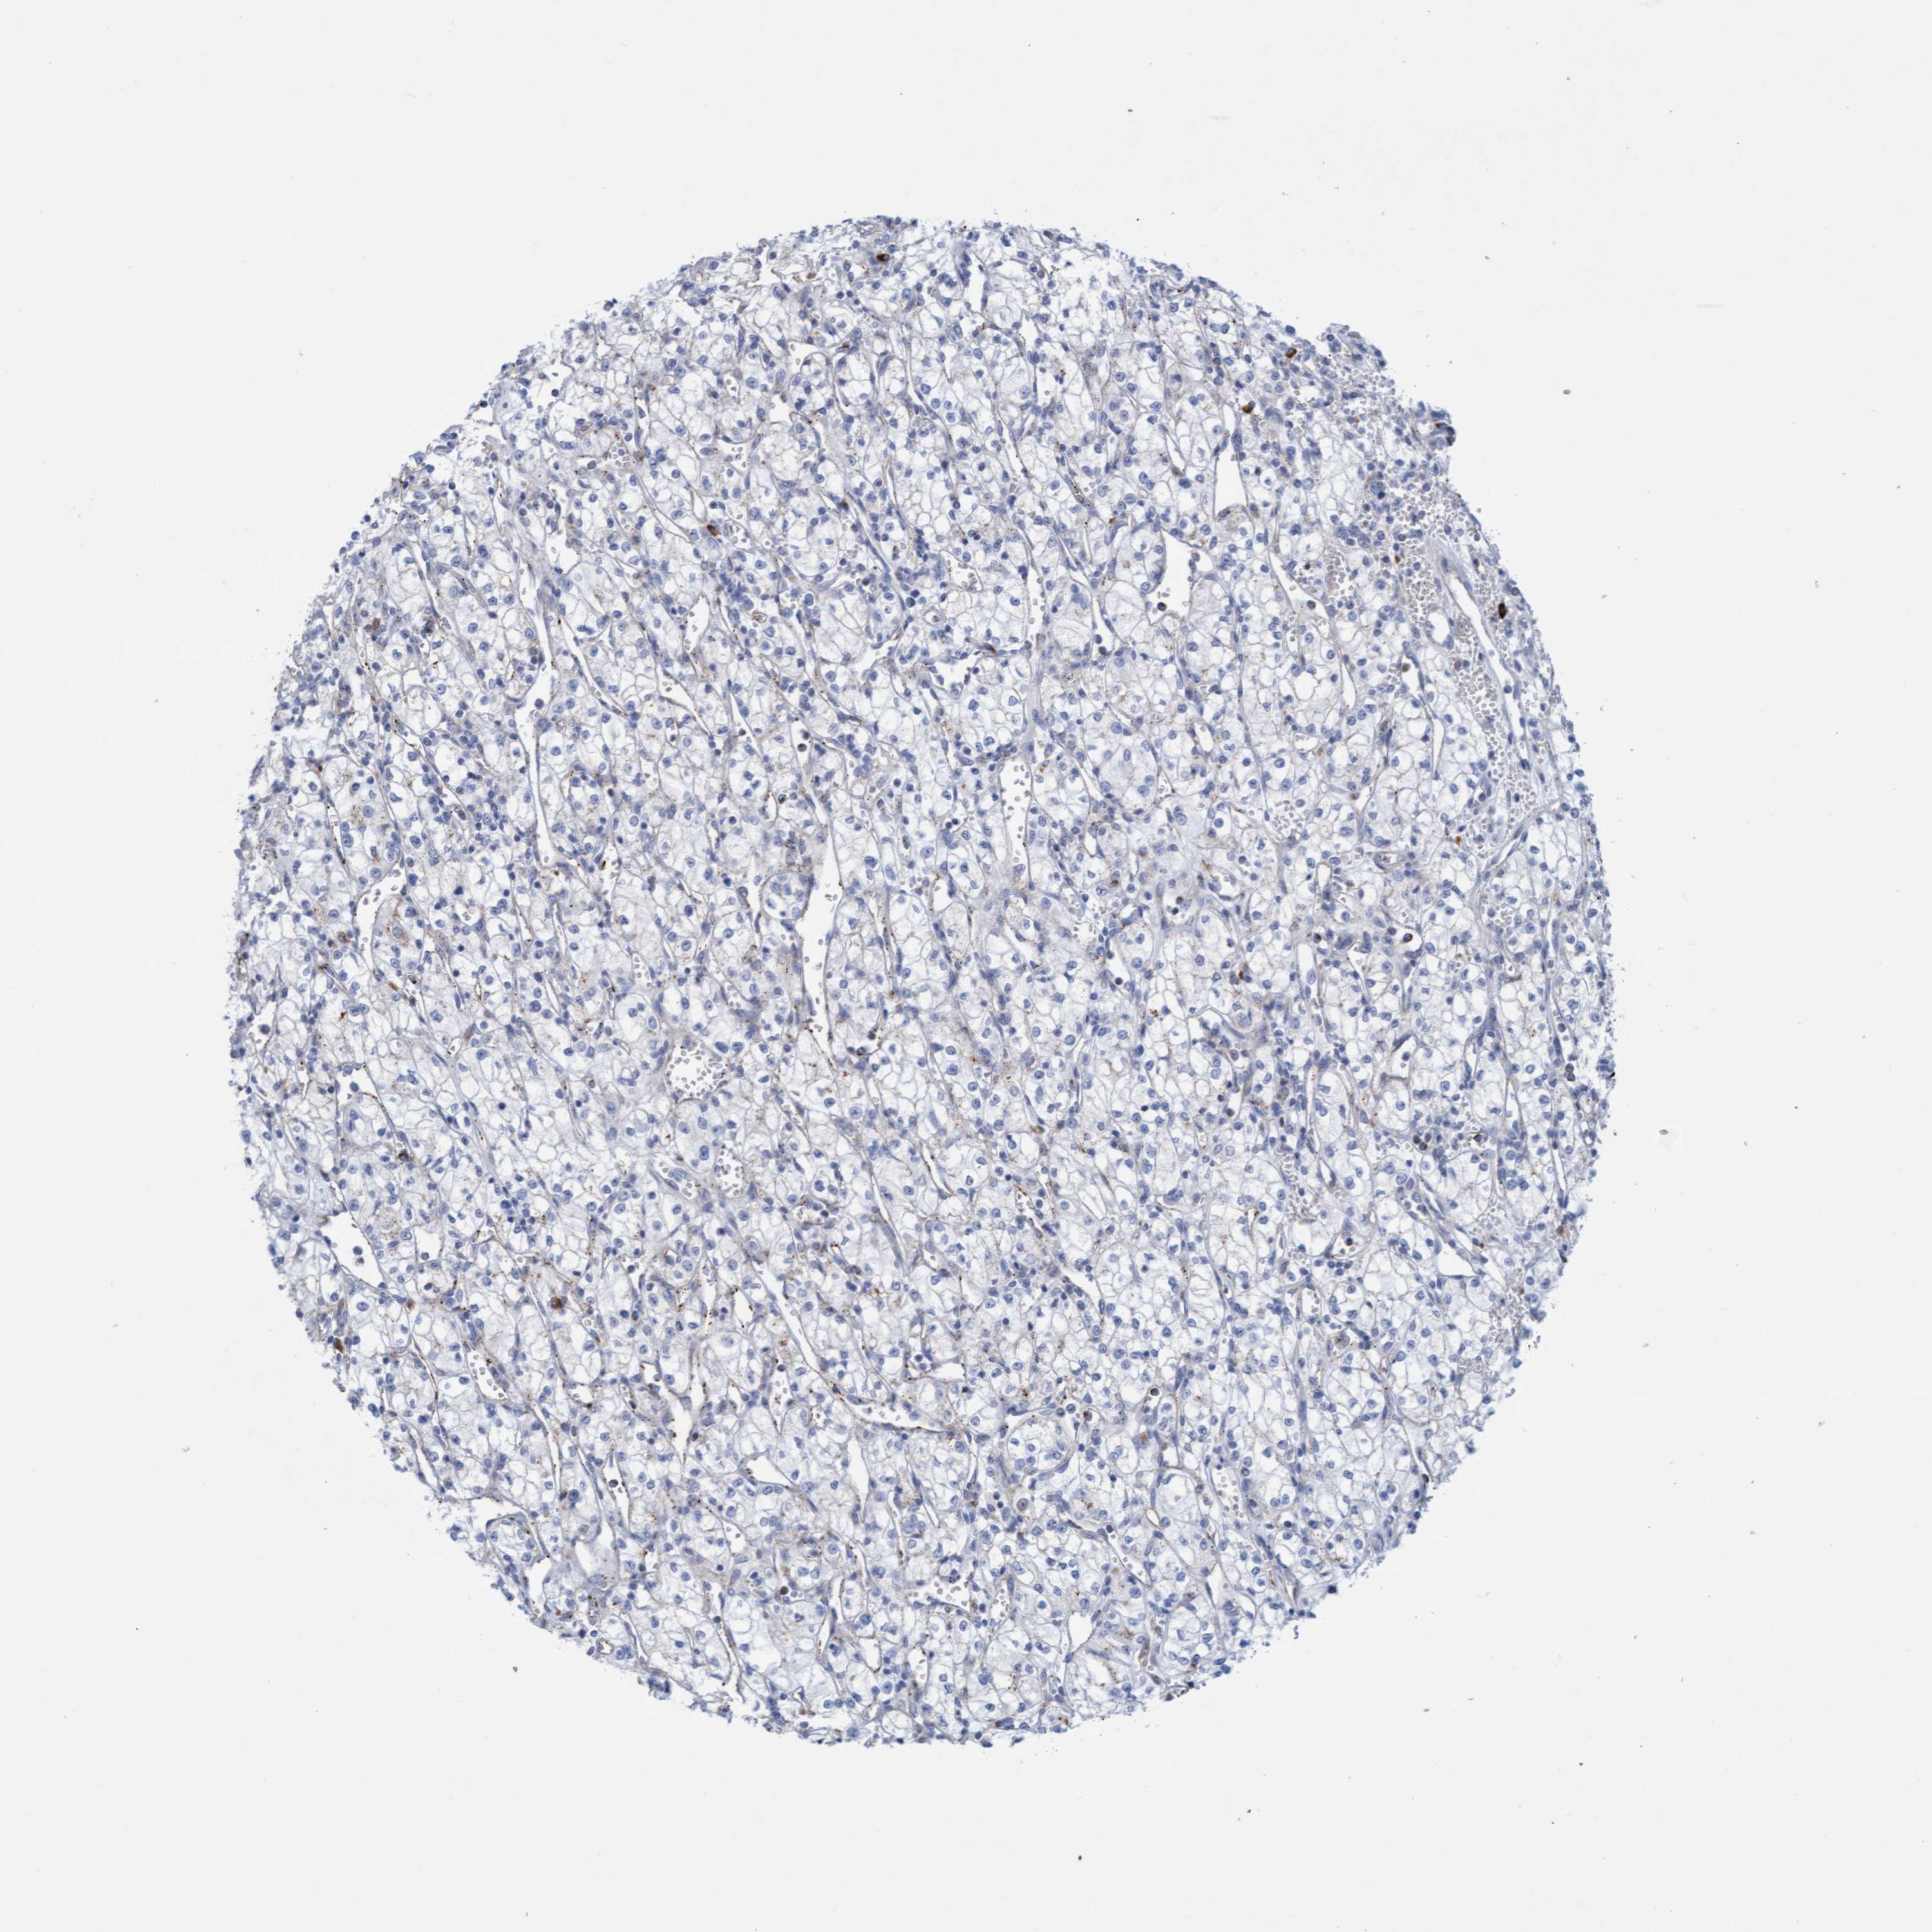

Average pTPM 15.7

Number of samples 521